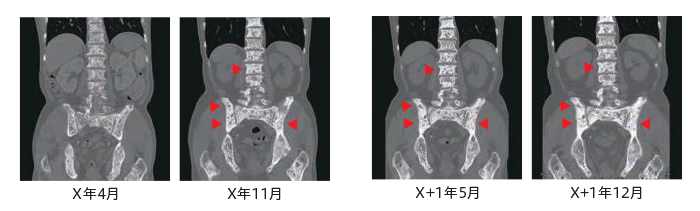

X年11月:実施したCTでは臓器転移はなく、リンパ節転移は完全奏効(CR:complete response)に至った。多発骨転移の治療を目的として塩化ラジウム(223Ra)による治療をX年12月からX+1年4月まで4週ごと、計6回行った。

X+1年5月:塩化ラジウム(223Ra)治療6回完遂後に施行した骨シンチグラフィでは骨転移の改善が認められた。またCTでも臓器転移も認められずリンパ節転移CRに変化がなく、骨転移部位には化骨化がみられた(

)。しかしながらPSAおよびALPは依然高値を示したため、 アビラテロン酢酸エステル(100mg)およびプレドニゾロン(10mg)を開始し、治療を継続した。

X+1年12月:骨シンチグラフィでは骨転移の改善は維持されており、CT所見上では臓器転移は認められず、リンパ節転移もCRで骨転移部位には化骨化がみられている(

)。